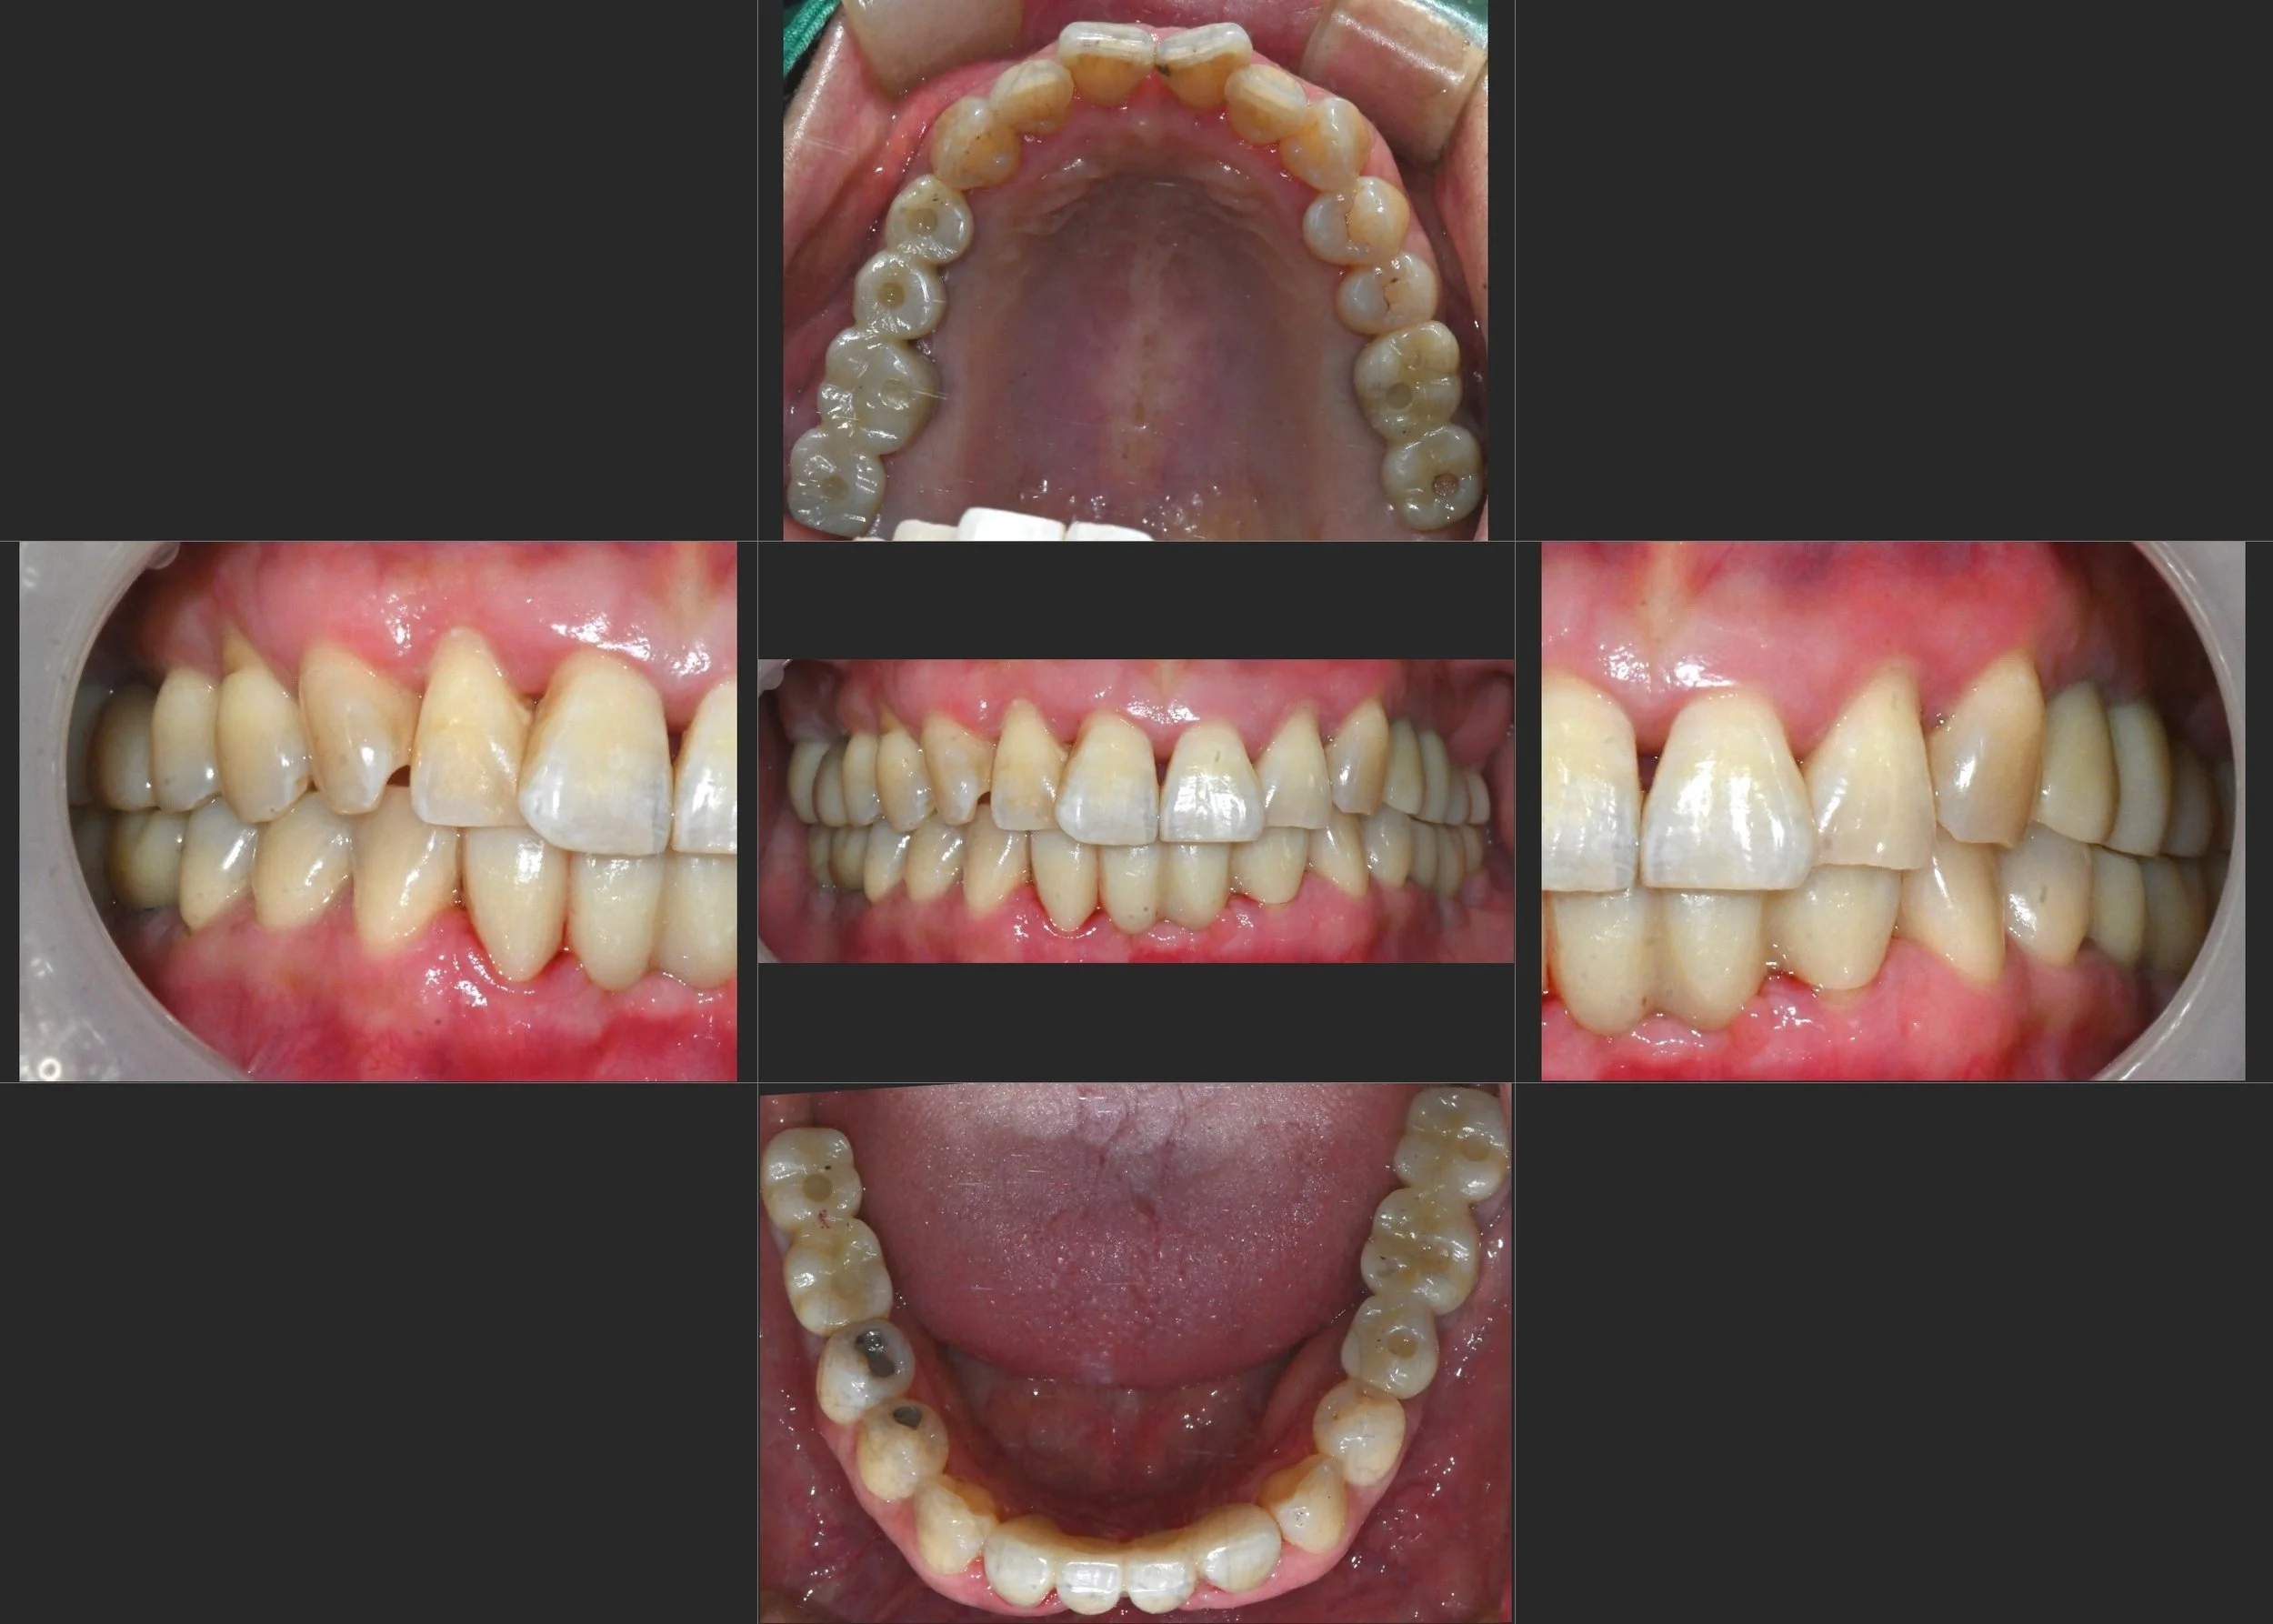

OPG - AFTER

INTRA ORAL - AFTER

• Restoration of posterior occlusion using implant-supported prostheses

• Establishment of a stable occlusal vertical dimension to protect anterior teeth

• Improvement of anterior esthetics following occlusal stabilisation

• Recovery of a maintainable and long-term functional oral condition

A staged, prosthetic-driven treatment plan was implemented.

Implant-supported restorations were used to re-establish posterior support and occlusal stability.

Following determination of an appropriate vertical dimension,

anterior restorations were designed to enhance esthetics while minimising functional overload.

The final outcome focused on predictability, load distribution, and long-term maintenance.